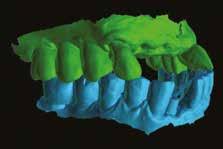

Eseguiti i rilievi diagnostici si propone in prima fase la estrazione del 12 e 11 dopo aver tagliato il ponte in bocca, mesialmente all’elemento 22, sostituendo provvisoriamente con protesi mobile gli elementi mancanti. Dopo le estrazioni e a guarigione dei tessuti avvenuta (foto 02), CBCT (foto 03) e rilievo dell’impronta ottica, si progetta l’inserimento di 2 impianti in Chirurgia guidata e contestuale GBR utilizzando sostituto osseo arricchito e inglobato in CGF, quello cioè che chiamasi Sticky Bone. Viene progettato in software di Chirurgia Guidata l’inserimento prima dei denti mancanti e poi dei 2 impianti in posizione ideale per la riabilitazione protesica. (fig. 04-05-06)

A progettazione implanto-protesica ultimata si disegna una dima chirugica che poi verrà stampata con Stampante 3D a tecnologia DLP. (fig. 07). L’intervento viene eseguito in anestesia locale con Articaina 1:200.000, si apre un lembo a tutto spessore e si posiziona la dima ad appoggio dentale, si inseriscono gli impianti programmati, si coprono alcune spire implantari esposte e si aumenta il volume osseo vestibolare con Sticky Bone. (fig. 08) A copertura della GBR si posiziona una membrana di CGF. Particolare attenzione viene posta nella sutura a più strati che ci dia contemporaneamente la certezza dell’immobilizzazione dell’innesto e della guarigione per prima intenzione della ferita. (fig. 09-10). Dopo circa 5 mesi si procede con la riapertura degli impianti (fig. 11) e dopo la guarigione dei tessuti si prende impronta ottica con Scan Bodies.

Si portano all’interno del Software CAD i files, si progetta un ponte avvitato che viene poi fresato con una fresatrice a 5 assi. Ottenuto il ponte questo viene poi incollato ai 2 TBase. Il giorno stesso dell’impronta il ponte viene montato in bocca. (fig. 12-13)